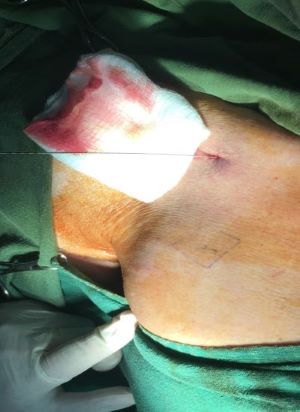

Patients were positioned supine, and vital parameters were evaluated on a monitor. All operations were done under local anesthesia. After double sterilization (alcohol and Betadine) of the right thorax and neck, local anesthesia (20 ml mepivacaine) was applied. A skin incision was made parallel to Langer’s lines, safe access to the right subclavian vein was performed by Seldinger technique10 (Venipuncture is performed under US guidance in 50 patients only (53.7%) according to the facility of the hospital with a micropuncture needle, Figure 1) until obtaining venous blood. Then the syringe was disconnected and a guidewire inserted downward. A small subcutaneous incision (2-3cm) was done at the upper chest wall, and the portal was implanted in a subcutaneous pocket with additional dissection (Figure 2).